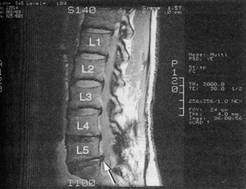

Caso 7 O Sr. E. A. é um homem branco, com 55 anos de idade, empregado como ferramentei-ro de uma grande corporação. Foi examinado, primeiro, por seu médico, em 11 de abril, quei-xando-se de dormência nos pés. A dormência já durava há vários meses. Na ocasião, determi-nou-se que o Sr. E. A. era alcoólatra, mas ele recusou tratamento para seu alcoolismo. Hoje, queixa-se de fraqueza geral e dormência nos membros inferiores, dizendo que seus sintomas pioraram desde a última visita médica. O Sr. E. A. não tem história de outros problemas mé-dicos graves. O exame físico mostrou pressão arterial de 155/95, sem outros achados. O exame neurológico revelou que o Sr. E. A. contava uma história coerente e concisa. Estava orientado quanto à sua pessoa, ao lugar e ao tempo. Lembrou-se dos três itens pedidos. Não foram encontradas anormalidades na função dos nervos cranianos. A marcha do Sr. E. A. era segura, mas com a base aumentada e atáxica. Tendia a bater os pés no chão, quando caminhava. Mos-trou-se incapaz de andar nos calcanhares e nas pontas dos pés. O exame dos sistemas motores mostrou que a força nas extremidades superiores era bilateralmente simétrica e normal (5/5). Não havia desvio, quando mantinha os braços esticados na frente do corpo. A força dos membros inferiores era simétrica, mas fraca ao teste direto de força (4/5). Com dificuldade, conseguia fazer flexão profunda dos joelhos. Não havia espasticidade ou rigidez. Volume muscular normal, sem atrofia aparente. Ausência de fasciculações ou outros movimentos a-normais. A pesquisa dos sistemas sensoriais mostrou que a percepção da picada de alfinete estava bilateralmente atenuada, e a sensibilidade vibratória, ausente, dos joelhos para baixo, inclusive nos pés. O Sr. E. A. não conseguia determinar a posição dos dedos dos pés, quando eram movimentados, passivamente, pelo examinador. Ao pedir-lhe que ficasse de pé sobre uma base estreita, ficava razoavelmente estável. Quando lhe foi pedido que fechasse os olhos, tornou-se instável, e teria caído, se não fosse amparado pelo examinador (teste de Romberg). As sensações a partir dos membros superiores eram simétricas e percebidas como normais. Ambos os reflexos aquileus (músculos gastrocnemius-soleus) apresentavam-se deprimidos (--). Os reflexos patelares (músculo quadríceps) e os do membro superior estavam normais. Os reflexos plantares eram flexores. As provas calcanhar-joelho, dedo-nariz, movimentos alternantes rápidos das mãos e o toque rápido dos dedos foram facilmente realizados. Ausên-cia de afasia; nistagmo optocinético presente em ambas as direções. Ausência de sinais atávi-cos. Não foram solicitados exames complementares. Evolução: O Sr. E. A. foi novamente encorajado a procurar tratamento para o alcoo-lismo e, de novo, recusou. Foram prescritos suplementos vitamínicos, e o paciente foi aconse-lhado a melhorar seu estado nutricional. Seu diagnóstico definitivo estabeleceu-se como poli-neuropatia de origem hipovitamínica. Caso 8 A Sra. N. B. é uma mulher branca, com 63 anos de idade, que foi ao médico de família queixando-se de dor na parte inferior das costas, que se estendia para o lado e para baixo, ao longo de sua perna direita. Caminhava, obviamente, mancando. A dor começou em abril e tem piorado. A Sra. N. B. relatou que a dor era intensa e que, depois de uma semana de repouso completo no leito, a dor permanecera sem diminuir. A Sra. N. B. não tem história de doença médica grave. O exame físico mostrou que a Sra. N. B. está em boa saúde física. Pressão arterial de 135/80. O exame neurológica revelou que a Sra. N. B. está orientada quanto à sua pessoa, ao lugar e ao tempo. Ao final do exame, lembrava-se dos três itens requisitados. Não foram encontradas anormalidades na função dos nervos cranianos. A Sra. N. B. caminhava mancando, favorecendo a perna direita. Podia andar nos calcanhares, mas tinha alguma dificuldade em andar na ponta dos pés, sendo incapaz de manter a extensão do pé direito. A avaliação da motricidade revelou que a força era 5/5, exceto nos músculos gastrocnemius-soleus direito, onde era 4/5. Não havia espasticidade ou rigidez. O volume muscular era nor-mal para uma mulher de sua idade. Ausência de atrofia óbvia. Ausência de fasciculações ou outros movimentos anormais. O exame dos sistemas sensoriais revelou sensibilidade amor-tecida à picada de alfinete, no bordo lateral da extremidade inferior direita e no pé. A Sra. N. B. sentia dor intensa quando sentada numa cadeira ou quando ficava de pé. Tinha mais con-forto deitada na cama, com os joelhos fletidos, apesar de, mesmo então, não estar livre da dor. A elevação passiva da perna estendida era limitada a 30º, pela dor, à direita. A perna esquerda podia ser elevada a 90º quase sem dor. Os reflexos de estiramento muscular estavam normais e simétricos, exceto o do tendão aquileu direito, no qual estava ausente. Os reflexos plantares estavam em flexão plantar, bilateralmente. Todos os testes cerebelares foram realizados sem dificuldade. Todos os testes parietais eram normais. Foi solicitada uma ressonância magnética da coluna lombo-sacra (vide figura), a qual revelou hérnia discal ao nível de S1, confirmando assim o diagnóstico de radiculopatia compressiva.